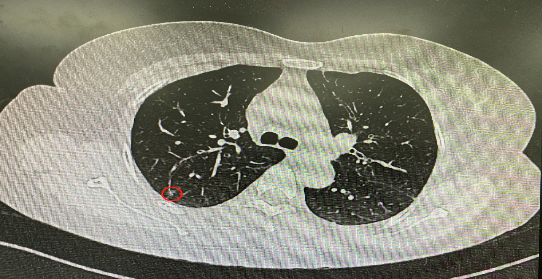

今年54歲的李女士(化名)7月初突然出現(xiàn)右上部腹痛,起初并未在意,以為稍作休息就會(huì)好轉(zhuǎn),但疼痛卻并未消退,持續(xù)了一個(gè)星期。李女士實(shí)在難以忍受,才在家人陪伴下來(lái)到西安國(guó)際醫(yī)學(xué)中心醫(yī)院就診。胸外科二病區(qū)崔凱主任接診患者后,詳細(xì)詢(xún)問(wèn)病情并查閱檢查資料,經(jīng)胸部HRCT檢查,結(jié)果提示:右肺上葉后段混合密度結(jié)節(jié)影,考慮原位癌可能,即將患者收入胸腔外科二病區(qū)住院治療。

經(jīng)與患者家屬溝通,崔凱主任決定行外科手術(shù)治療。為達(dá)到精準(zhǔn)切除,術(shù)前需進(jìn)行肺小結(jié)節(jié)切除前定位。由于結(jié)節(jié)位于右肺上葉后段,傳統(tǒng)經(jīng)胸外穿刺術(shù)無(wú)法抵達(dá)病灶。崔凱主任與呼吸內(nèi)科一病區(qū)歐陽(yáng)海峰主任討論后,決定擬行LungPro全肺診療導(dǎo)航下染色定位。即術(shù)前通過(guò)Lung Pro導(dǎo)航規(guī)劃染色位置,經(jīng)Lung Pro實(shí)時(shí)引導(dǎo)支氣管鏡抵達(dá)既定位置,注入亞甲藍(lán)染色劑標(biāo)記結(jié)節(jié)位置。

使用術(shù)前規(guī)劃系統(tǒng)重建全肺3D模型,并于外科醫(yī)生討論染色位置,最終確定標(biāo)記染色點(diǎn)—右肺上葉后段b亞段(RB2b)。術(shù)中使用P290(4.9mm外徑)標(biāo)準(zhǔn)支氣管鏡,根據(jù)導(dǎo)航術(shù)前規(guī)劃路徑,Lung Pro實(shí)時(shí)導(dǎo)航下,GS鞘管進(jìn)入RB2b遠(yuǎn)端官腔外病灶并注射亞甲藍(lán)染色劑。